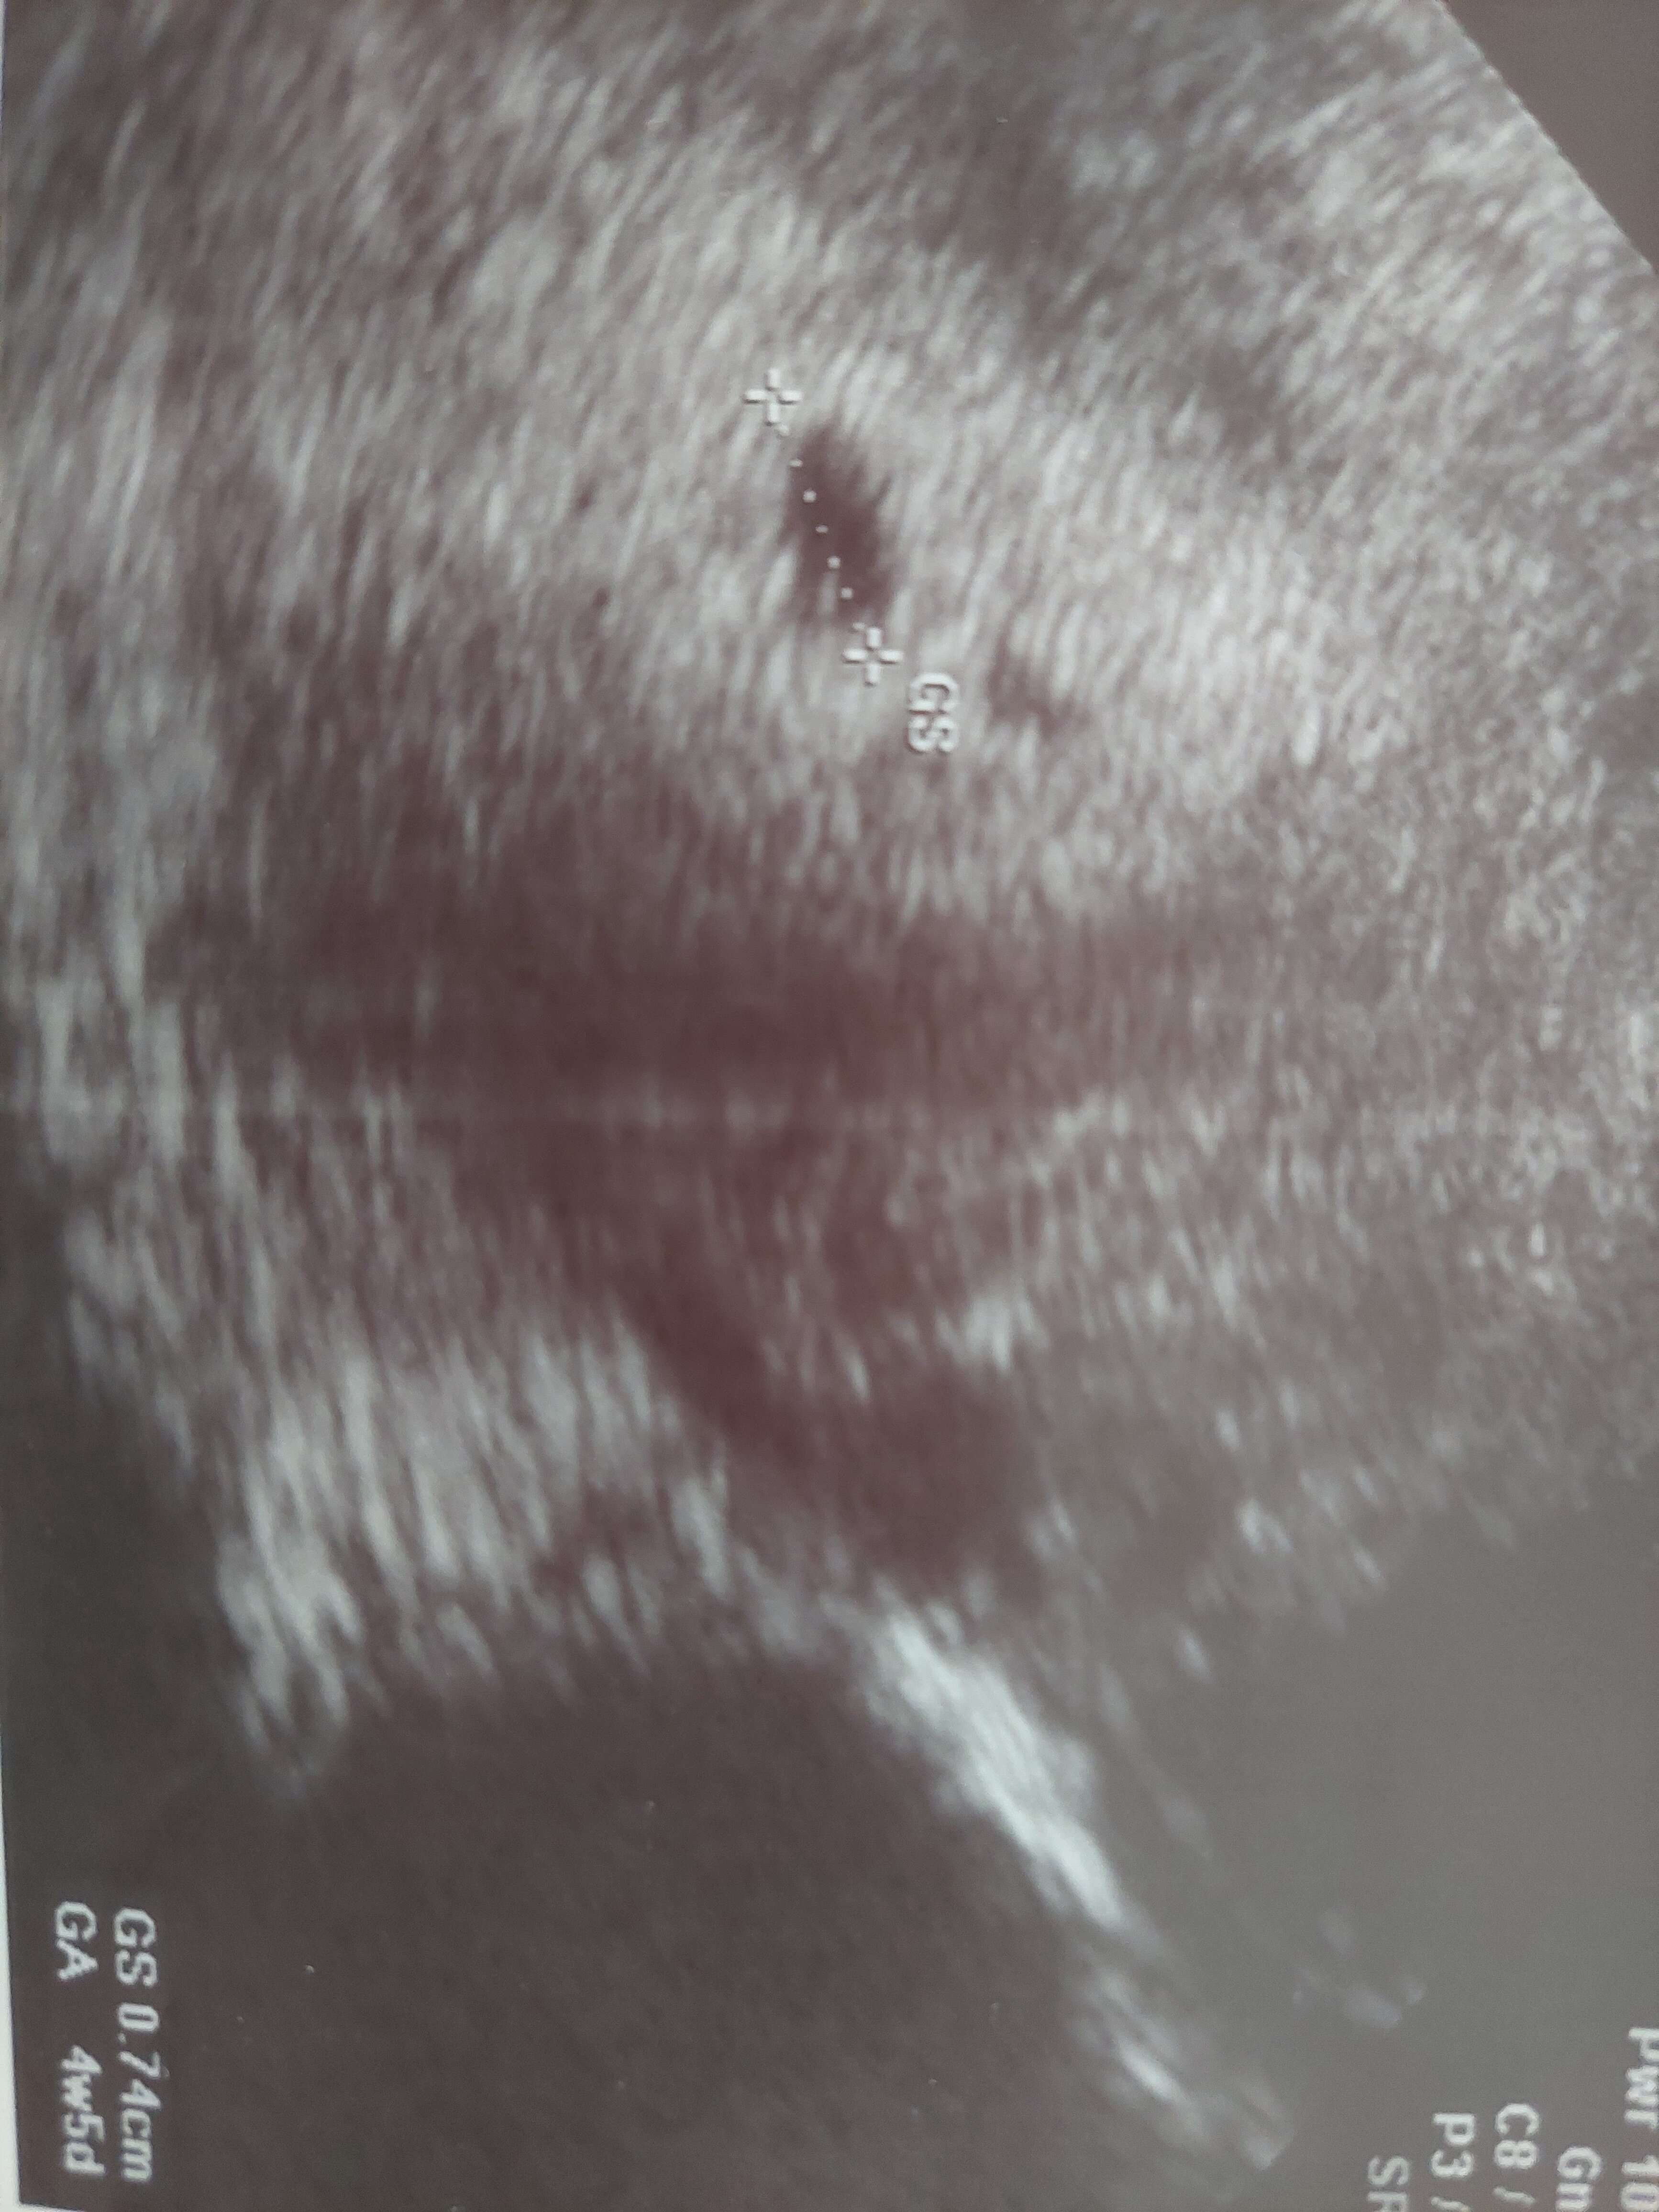

Hej, w domu na wydruku usg zobaczyłam że obok pecherzyka jest jakiś mały ciemny obszar o nieregularnym kształcie. Czy to może być krwiak? Lekarz nic nie mówił. W usg z poprzedniej ciąży nic takiego nie miałam ale też byłam pierwszy raz na usg dużo później.

• 20220713_065723.jpg

20220713_065723.jpg

1,9 MB · Wyświetleń: 101